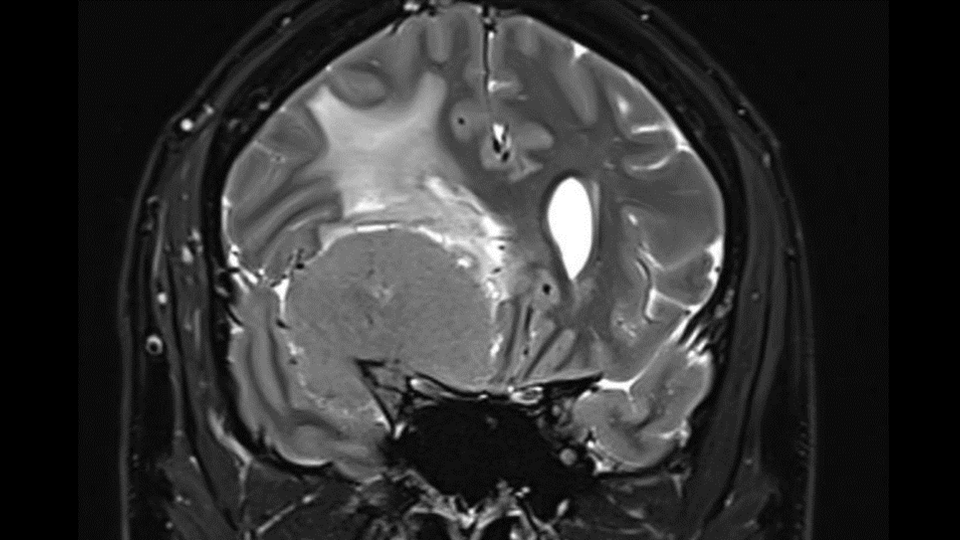

Given these findings, this patient was discussed with the neurosurgical on call team. He was commenced on oral dexamethasone and transferred urgently to the tertiary neurosurgical centre for urgent review. Magnetic Resonance Imaging (MRI) (Figure 2) of his brain and orbits detailed further significant vascular involvement, including invasion of the right cavernous sinus, encasement of the right supraclinoid ICA, proximal right M1 MCA and foetal posterior cerebral artery (PCA). The A1 ACA segment was absent or occluded and the right M1 MCA was severely stenosed. The mass directly abutted the lateral surface of the right optic nerve but without evidence of involvement or chronic nerve atrophy (Figure 3).

Formal ophthalmology assessment noted improvement in his VA to 6/6 bilaterally with grade 1-2 optic disc swelling in the left eye without evidence of vascular changes and normal appearance of the right optic disc. Operative management involved craniotomy with dissection of the tumour, retrograde to the direction of the MCA. Gradual tumour bulk removal allowed for visualisation of the optic nerve, ICA, ACA, MCA, posterior communicating artery (PCOM) and anterior communicating artery. Despite the operation’s success in removing the majority of the tumour bulk, the mass was closely adherent to the MCA (and associated perforators),  avernous sinus and right posterior communicating artery. These sections were unable to be completely excised. Biopsies were taken, demonstrating tissue consistent with World Health Organisation (WHO) grade 1 meningioma without invasion into brain parenchyma.